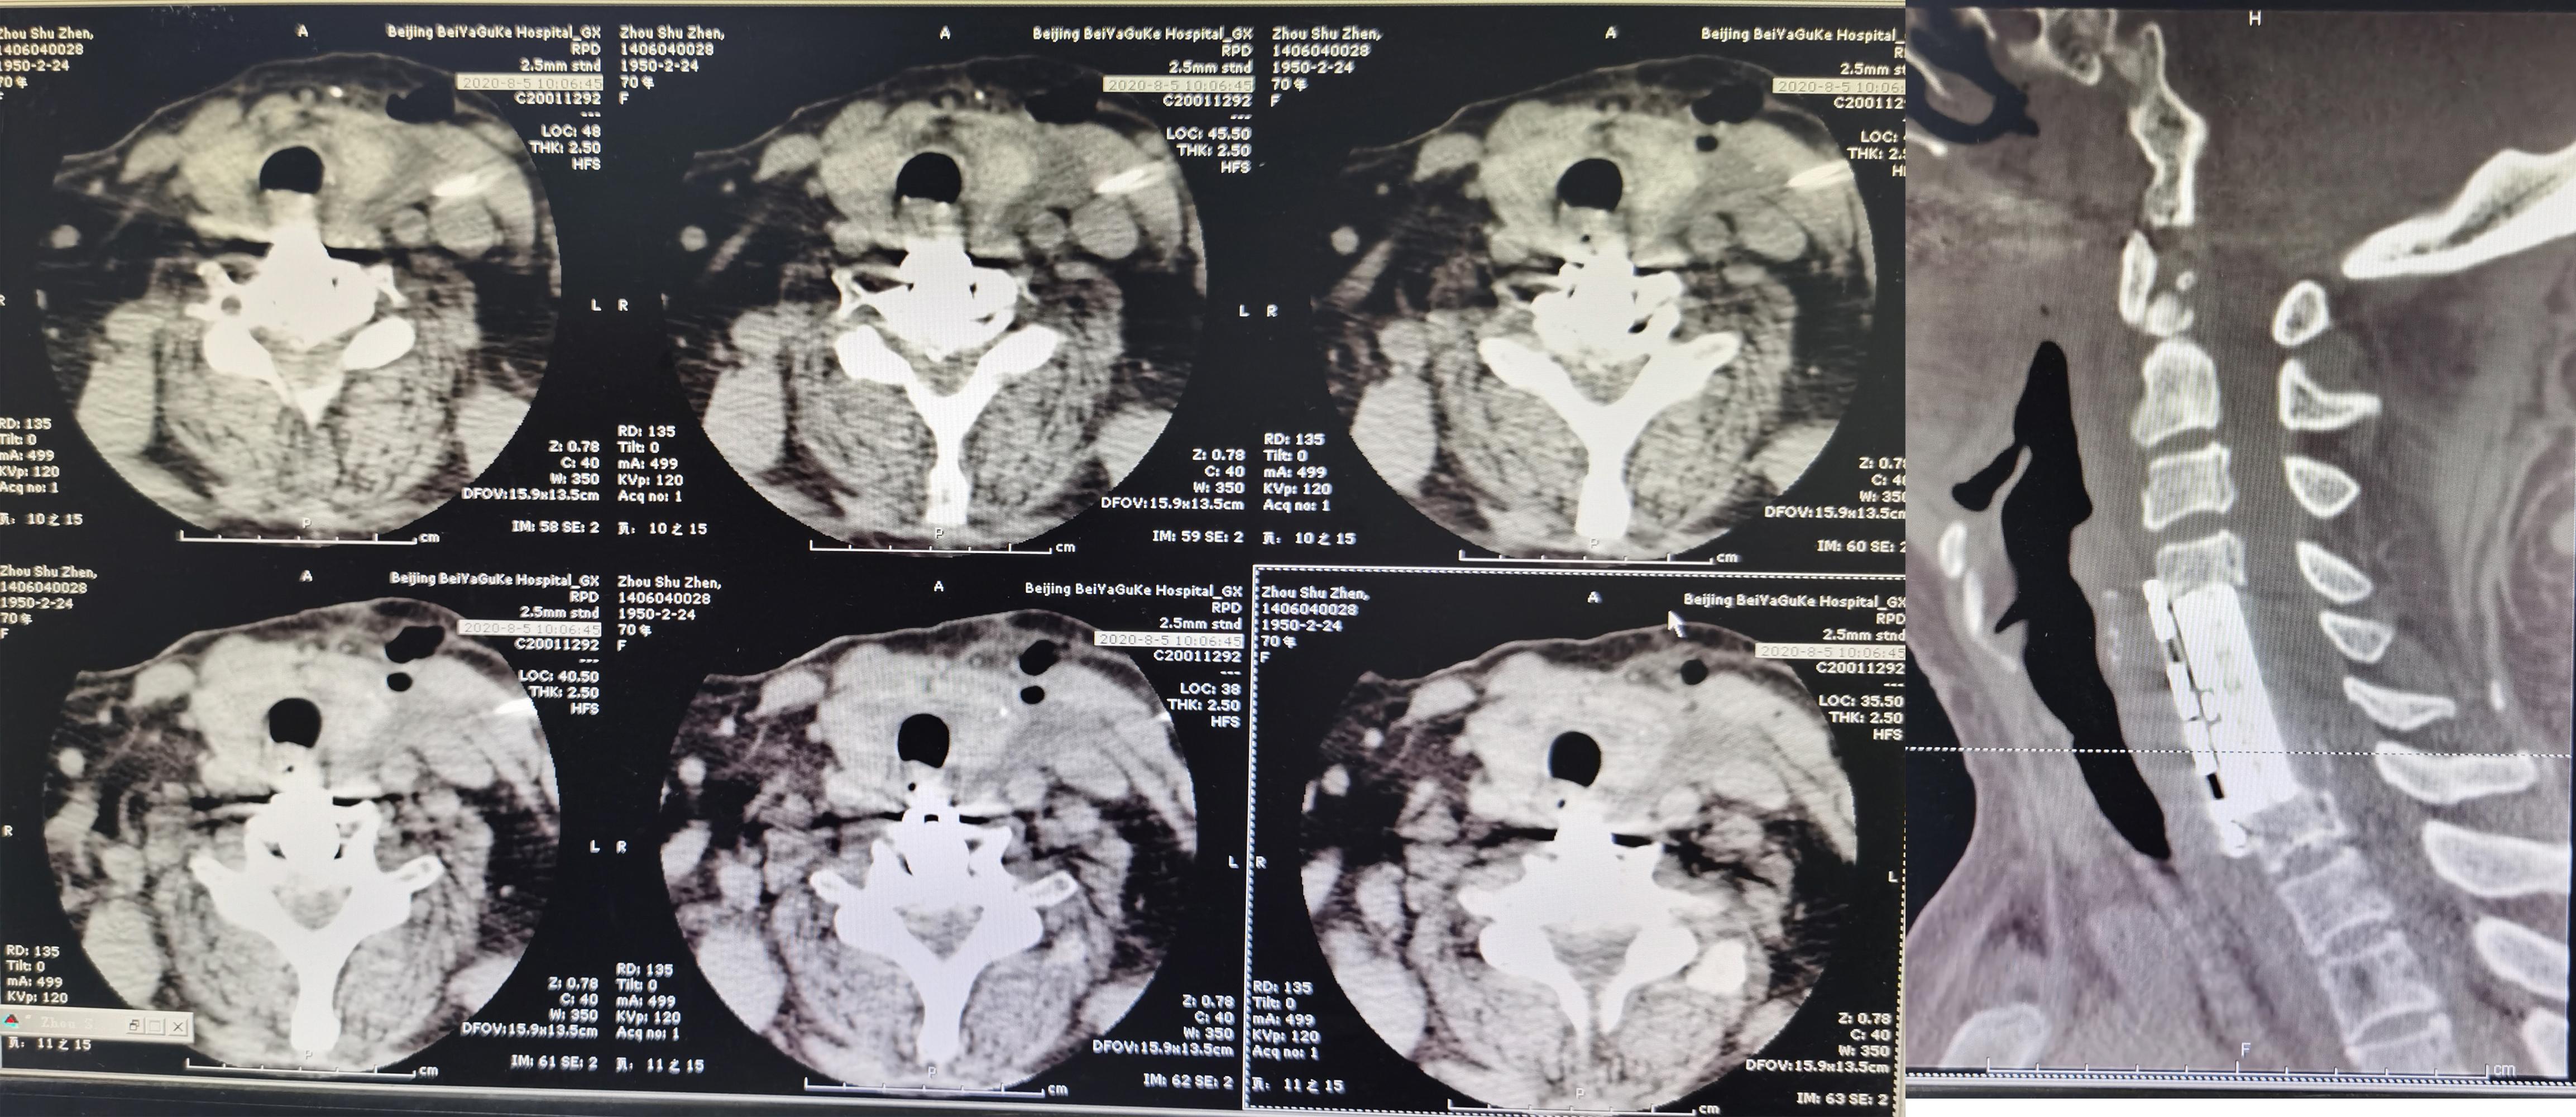

2020年8月4日(即第一次行前路颈5-6椎间盘切除椎间植骨融合内固定术后第114天),再次行颈椎前路颈5、颈6锥体次全切、人工锥体钛板螺钉内固定术,2020年8月5日(即第二次颈椎病术后第1天)复查颈椎平片及颈椎CT示椎管狭窄解除,人工椎体位置良好( 图-6、图-7 )。

图-7: 2020年8月5日颈椎CT